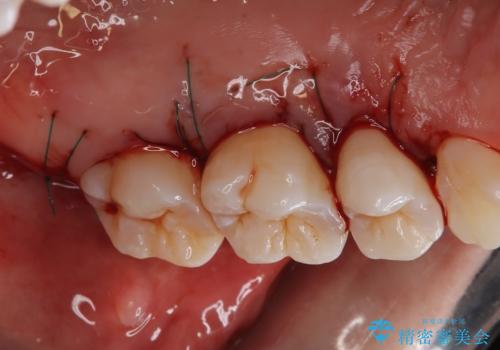

- 定期的にクリーニング(保険適応)に通って頂いている患者さんです。歯周ポケットが4ミリあったため歯茎を開いて歯石を除去するためにオープンフラップ術を行うことにしました。

歯周ポケットがそれほど深くない患者さんでしたが、いざ歯茎を開いてみるとそこにはたくさんの歯石がありました。もし歯周ポケットが4ミリだからと言って放置していれば数年後には、沢山の骨が無くなっていたことが予期出来ます。現段階で歯茎の下にある歯石を除去することにより骨が無くなることを予防する事が出来ました。

- 外科手術のため、術後に痛みや腫れ、違和感を伴います